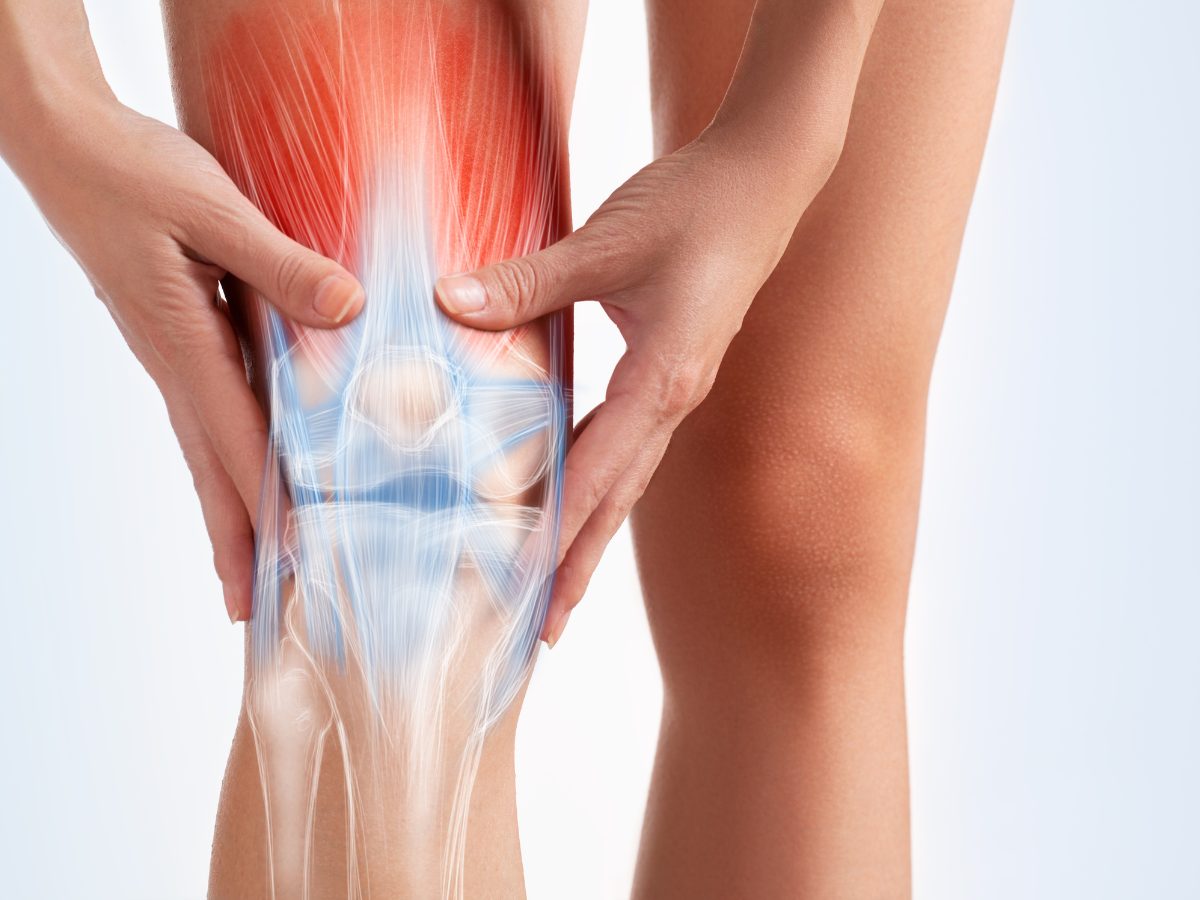

Анатомические рисунки суставов человека

:max_bytes(150000):strip_icc()/knee-anatomy--artwork-452427829-599d8b9b22fa3a0011f2030d.jpg)